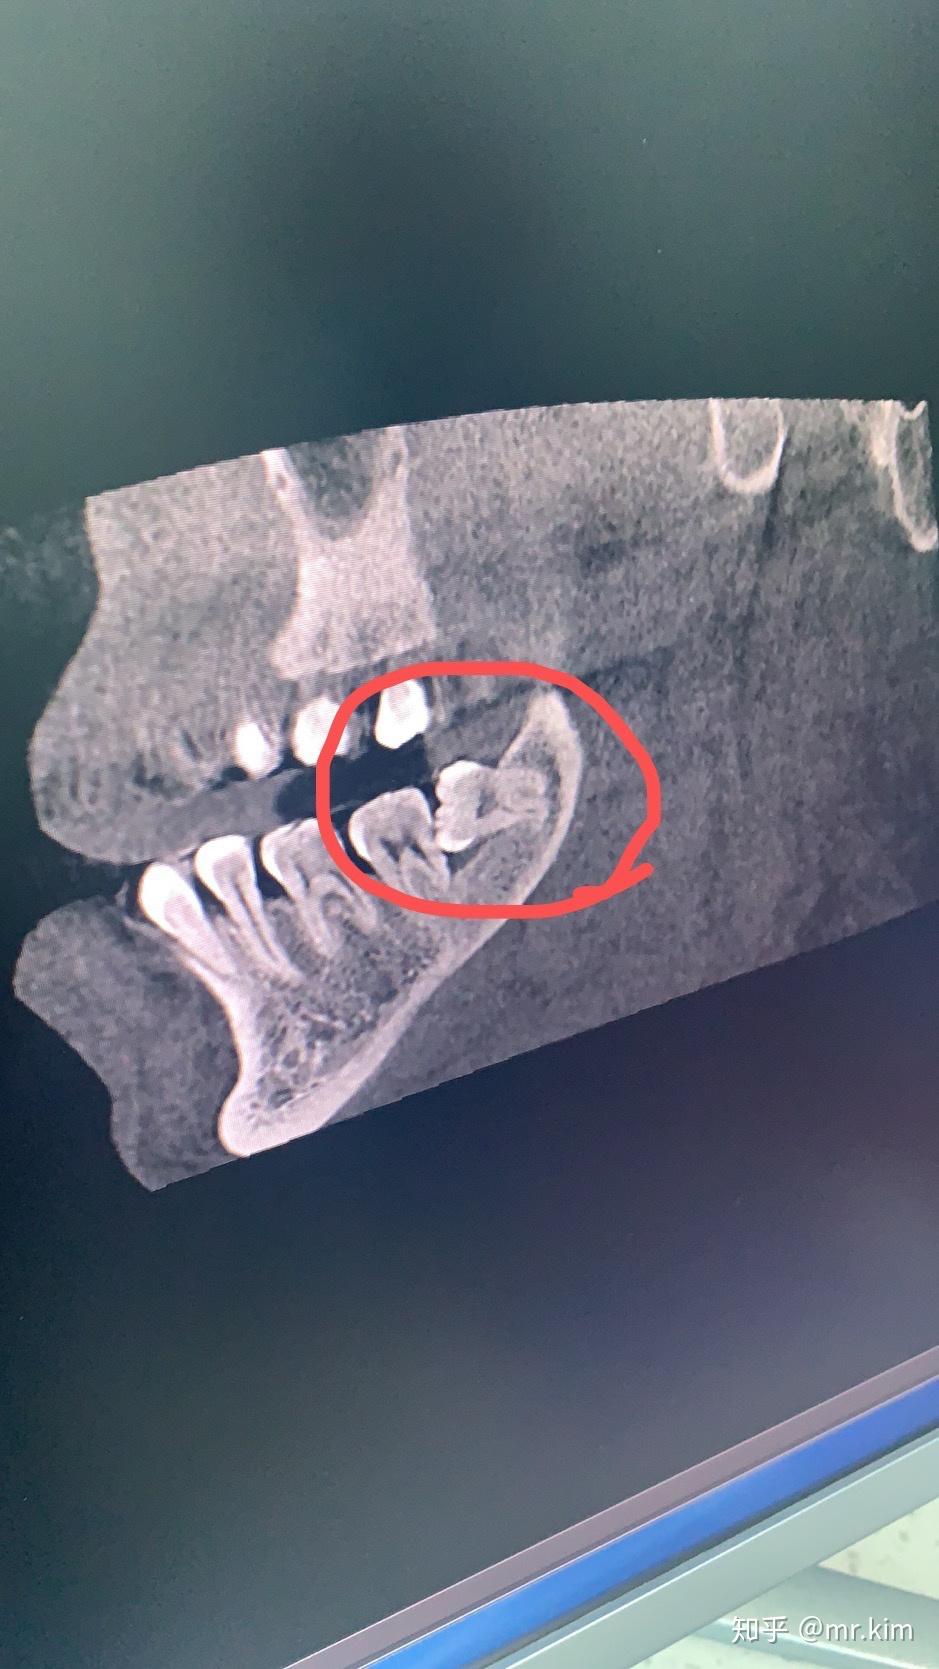

难度大不大牙!拔智齿.

智齿的术前阻力评估才能实现微创拔牙